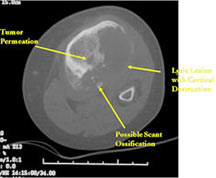

- Osteoid usually not discernible on X-ray but scant and faint lace-like osteoid may be detectable on a CT scan

- MRI and CT are also useful for demonstrating the local extent of the tumor and any soft tissue mass

- CT also useful for demonstrating scant osteoid production